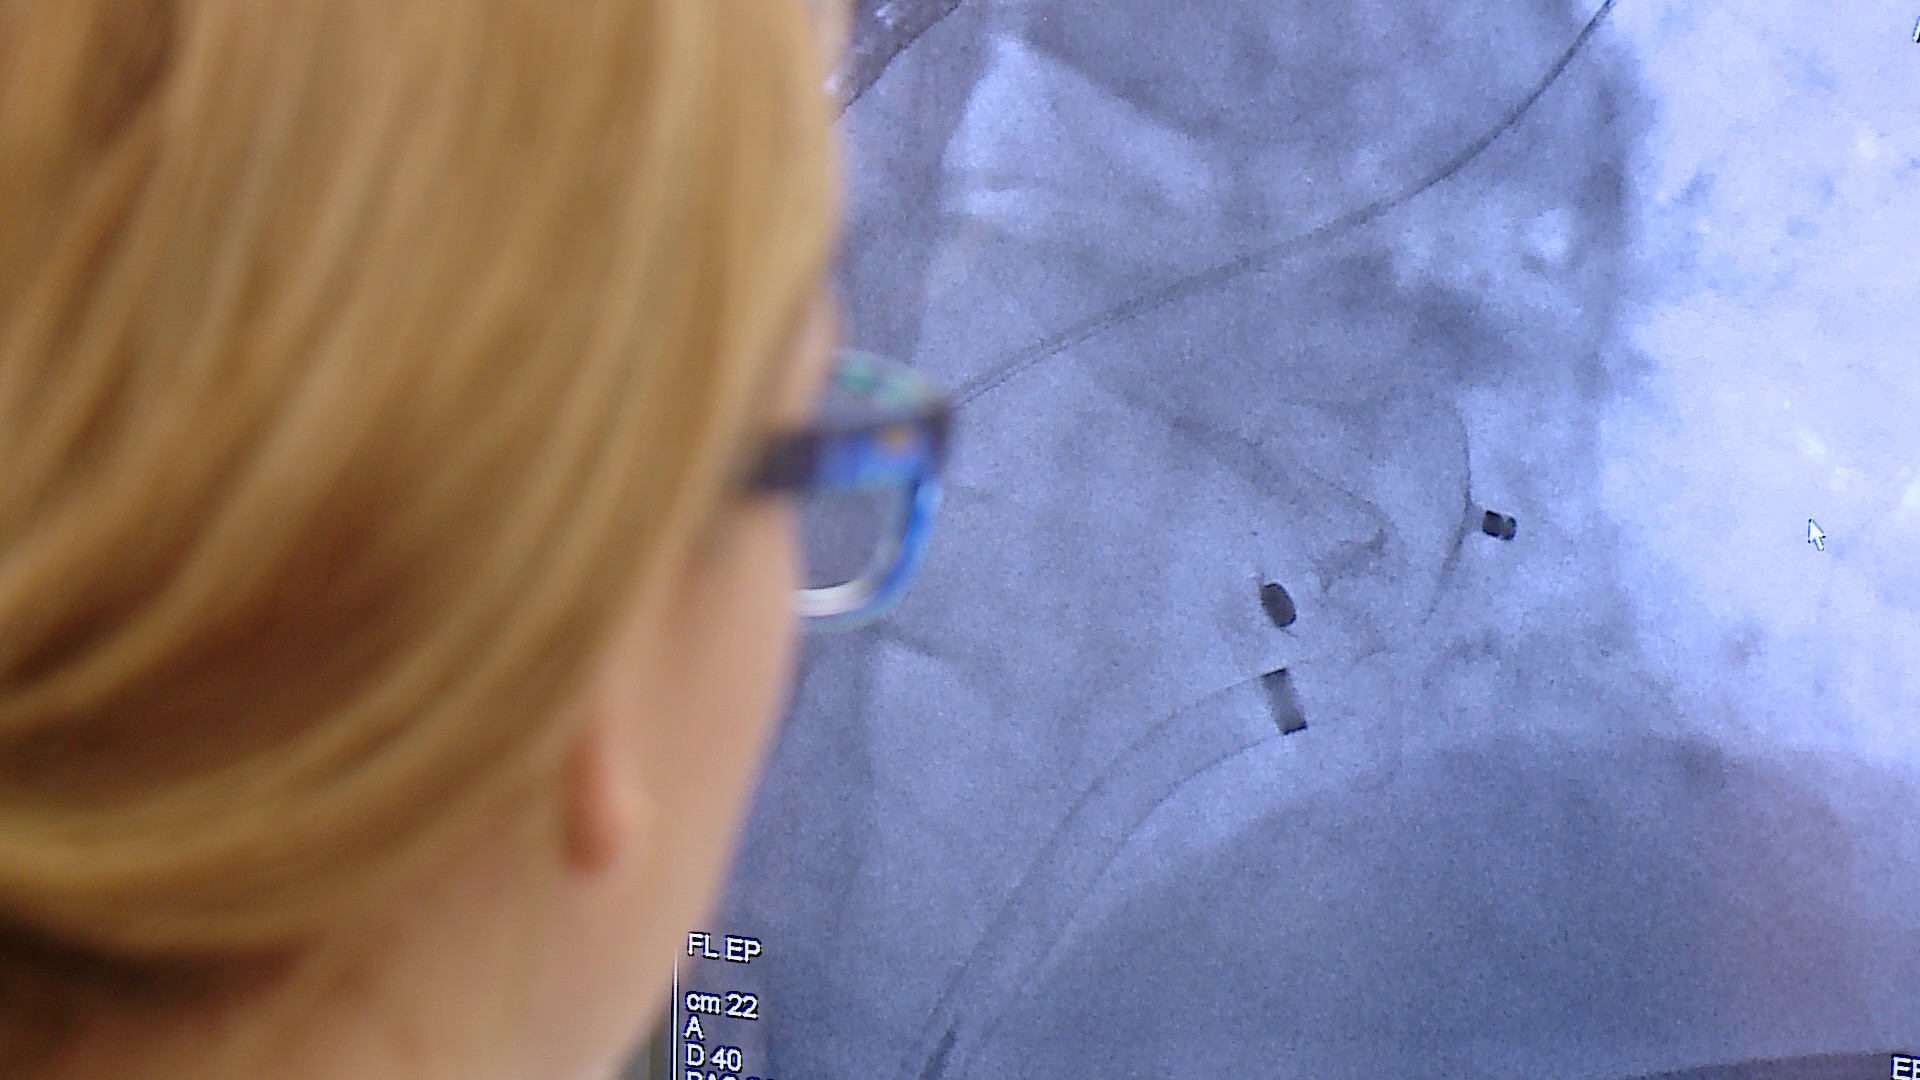

Zabieg polega na wprowadzeniu przez żyłę w pachwinie specjalnego okludera i umieszczeniu go w lewym przedsionku serca. Zabieg jest wykonywany w znieczuleniu płytkim ogólnym i trwa około godziny. Dzięki temu pacjent nie musi być hospitalizowany przez kilka dni.

Pierwsi trzej pacjenci zostali zoperowani w poniedziałek (25 czerwca) pod okiem profesorów ze Śląskiego Centrum Chorób Serca w Zabrzu.

Wszyscy pacjenci czują się dobrze i po 24-godzinnym pobycie w szpitalu zostali wypisani do domu – mówi dr Łukasz Lewicki, kierownik Pracowni Hemodynamicznej na Oddziale Kardiologii Szpitala w Wejherowie. – Nie udałoby się to bez obecności i wsparcia zespołu kardiochirurgów, którzy od ubiegłego roku działają w naszym szpitalu. Są niezbędni, bo wykonywane przez nas zabiegi są inwazyjne i dotyczą pacjentów wysokiego ryzyka, które są obarczone ryzykiem powikłań – dodaje.